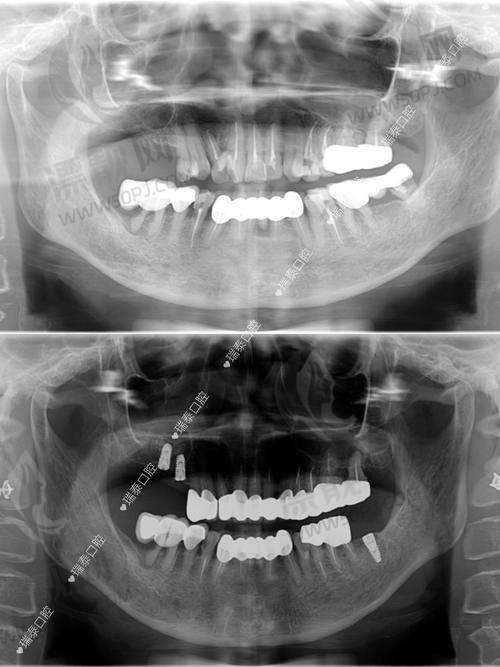

看点解读: 这家医院虽以综合性驰名,但口腔科独立门诊区域大,尤其在牙体修复、种植牙方面发展较早,与多家品牌合作进行即刻种植等手术操作。